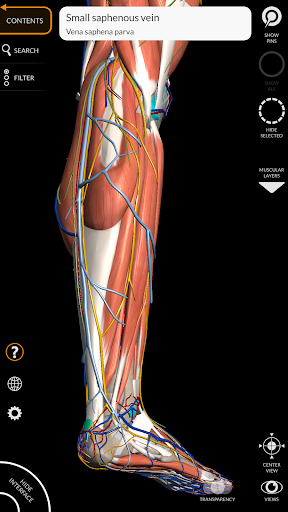

"Anatomy 3D Atlas" vous permet d'étudier l'anatomie humaine de manière simple et interactive.

Grâce à une interface simple et intuitive, il est possible d'observer chaque structure anatomique sous n'importe quel angle.

Les modèles anatomiques 3D sont particulièrement détaillés et avec des textures jusqu'à une résolution de 4k.

La subdivision par régions et les vues prédéfinies facilitent l'observation et l'étude de parties individuelles ou de groupes de systèmes et les relations entre différents organes.

MODÈLES ANATOMIQUES 3D

• Système musculo-squelettique

• Système cardiovasculaire